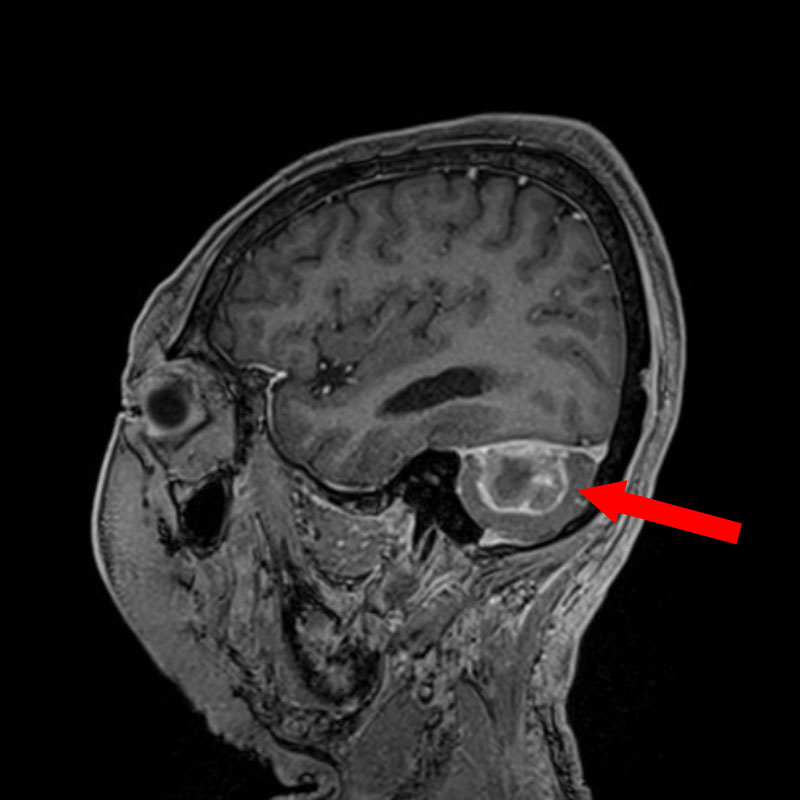

断層撮影

手術前1